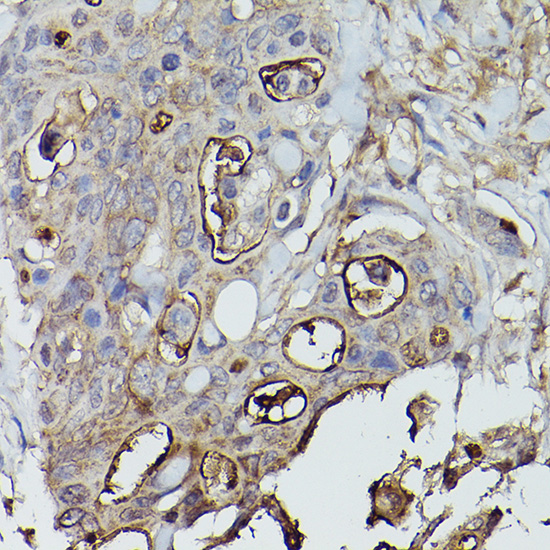

Immunohistochemistry of paraffin-embedded human colon carcinoma using Alkaline Phosphatase (ALPL) Rabbit pAb.